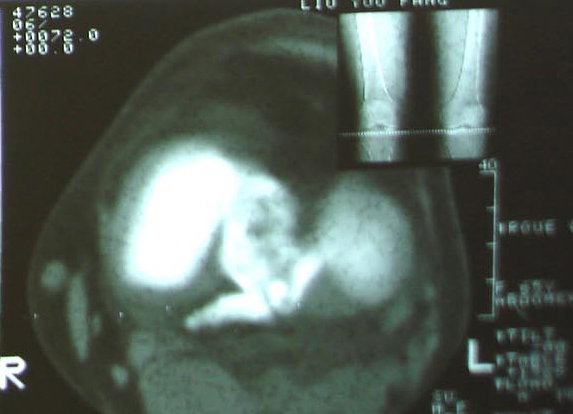

标题: 现将mri结果公布

手术证实是后交叉韧带胫骨附着处撕脱骨折。

术中用可吸收螺钉固定。